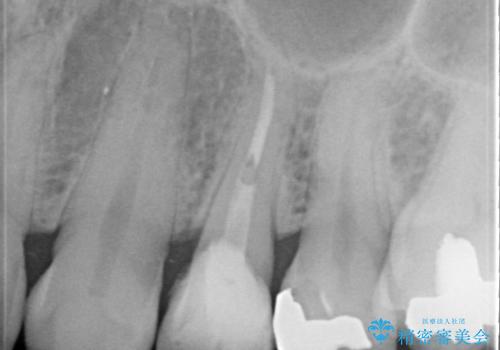

- 歯肉の下まで深く歯が折れたことを主訴に来院された患者様です。

かかりつけ医にて応急的に修復してますが根本的な治療を希望され、矯正的挺出を行ったのち、歯周外科を行い、歯冠修復をしております。

歯肉縁下の水平破折をきちんと治療するためには時間も費用もかかります。